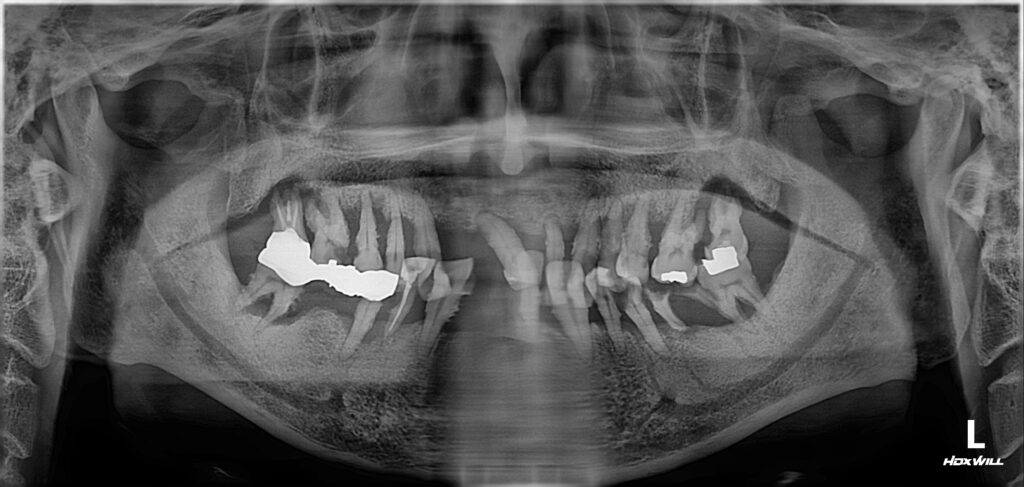

입안 상태를 보니 살릴 수 있는 치아가 하나도 안 보일 정도로 많이 손상되어 있었습니다.

이제 안 좋은 치아들, 그리고 거기에 붙어있는 염증조직들 그리고 세균 덩어리들 모두 제거한 뒤 임플란트 치료를 통해서 깨끗하고 가지런한 치아로 만들어드리기로 했습니다.

염증이 너무 심했기 때문에 발치하면서 바로 임플란트를 심지 않았고 발치 후 2개월 정도를 기다려서 염증이 다 없어지고 난 뒤 임플란트 수술을 하기로 했습니다.

염증으로 뼈가 많이 손상되어 있긴 했지만 뼈의 폭(너비)이 충분해서 뼈이식은 따로 할 필요가 없었습니다. 상악동 거상술 역시 필요치 않았습니다.